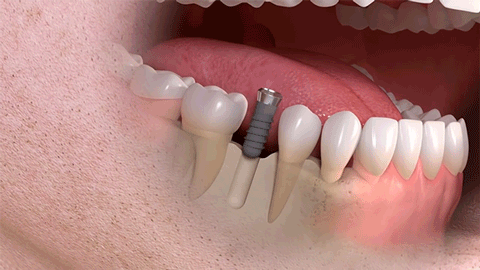

(单颗种植示例)

种植牙是医学界公认的理想修复方式,被誉为“人类的第三副牙”。相比活动假牙不舒服、难清洗、容易引起口腔黏膜病变,种植牙更稳固耐用,舒适美观,咀嚼功能好,一次种植,终生受用。种植牙不仅是中老年人的专利,年轻人因意外、牙病等造成牙齿缺失,也能够通过种植牙进行修复治疗,重获美丽笑容。